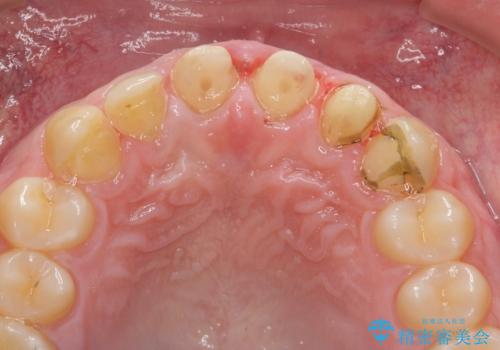

- 「前歯の見た目、歯ぐきの腫れを改善したい。」と希望され来院されました。

前歯には接着性の維持装置や、中途半端な形の連結クラウンが装着され、清掃性が悪く歯ぐきの腫れや、歯ぐきの形態の不揃いが認められました。